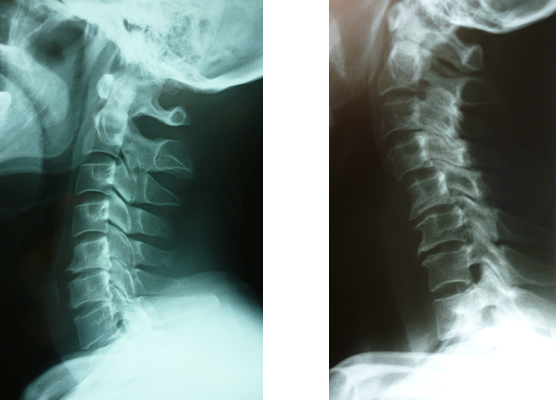

『カバンの持ち方、仕事の内容、片寄ったスポーツ・習い事』等により頸椎関節、肩関節へと波及していきます。やがて筋硬結、靭帯硬化と共に長い年月をかけて骨の変形が始まります。長い間頸椎X線撮影をして来ましたが徐々に変形は始まっています。変形性頸椎症に移行する前に早めの対策が必要だと痛感しています。

ストレートネックにもなり腰椎にも負担が掛ります。生理的自然弯曲に努め自然体で過ごされる事が望ましいです。意外と平背の方『姿勢美人』は頭痛、めまい、自律神経に影響が及んで不定愁訴があり、又、腰痛患者が多いのも特徴です。